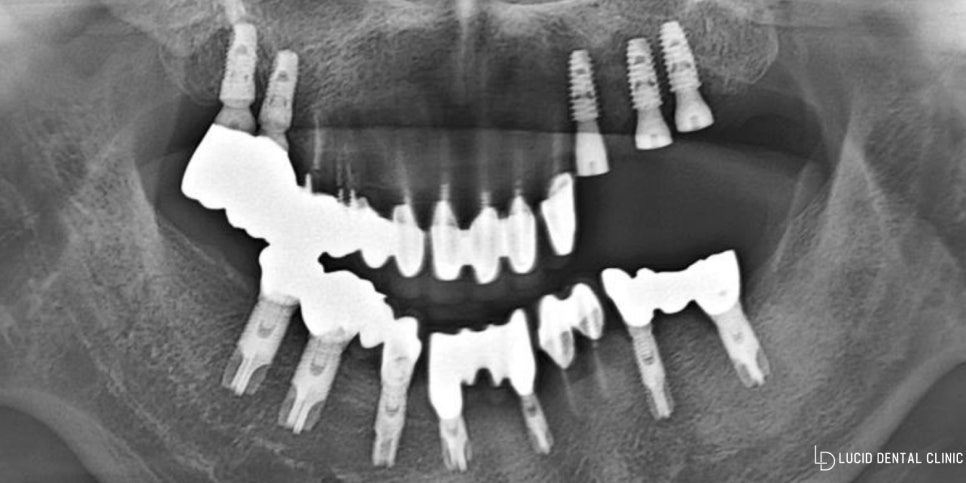

크게 수술 과정에 있어

걸릴만한 것이 없었기에

깔끔히 픽스처 3개를 잘 심을 수 있었습니다.

다만, 임플란트 수술 후

잇몸뼈와 골결합이 이뤄지는 기간 및 크라운 제작을

기다리는 기간을 가지게 되었는데요.

그럼 이런 상태로 집을 가야 되는지?

라는 질문에 그 위로 임시 보철을 씌워드릴 것이니

크게 걱정하실 필요없다는 답변을 드릴 수 있습니다.

이것은 위아래 교합이 맞는지

확인을 위하는 용도로 사용되며,

개인에 맞는 맞춤 형태로 진행할 수 있도록

조정하는 기간으로 보면 되겠습니다.